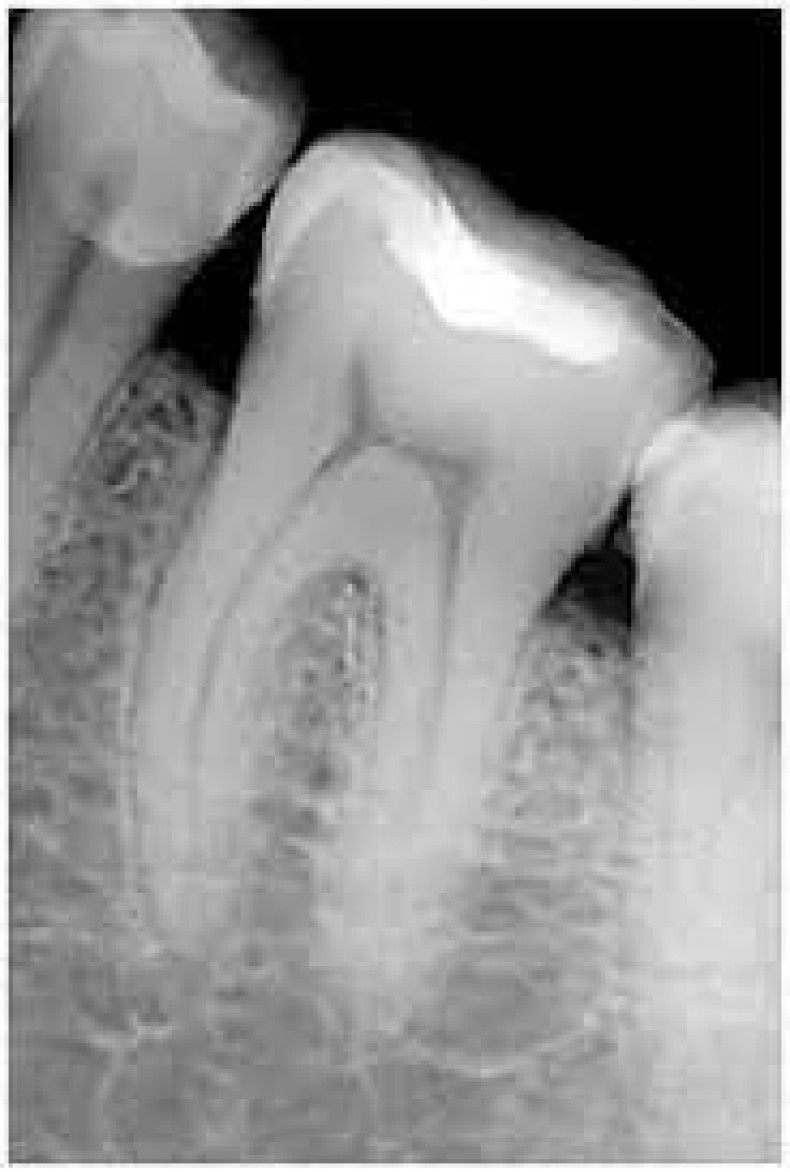

Прицельный снимок зуба, или визиография, это рентгеновский снимок, который позволяет получить детальное изображение одного или нескольких зубов и окружающих их тканей. Это важный диагностический инструмент в стоматологии, используемый для выявления кариеса, проблем с корневыми каналами, заболеваний десен и других патологий.